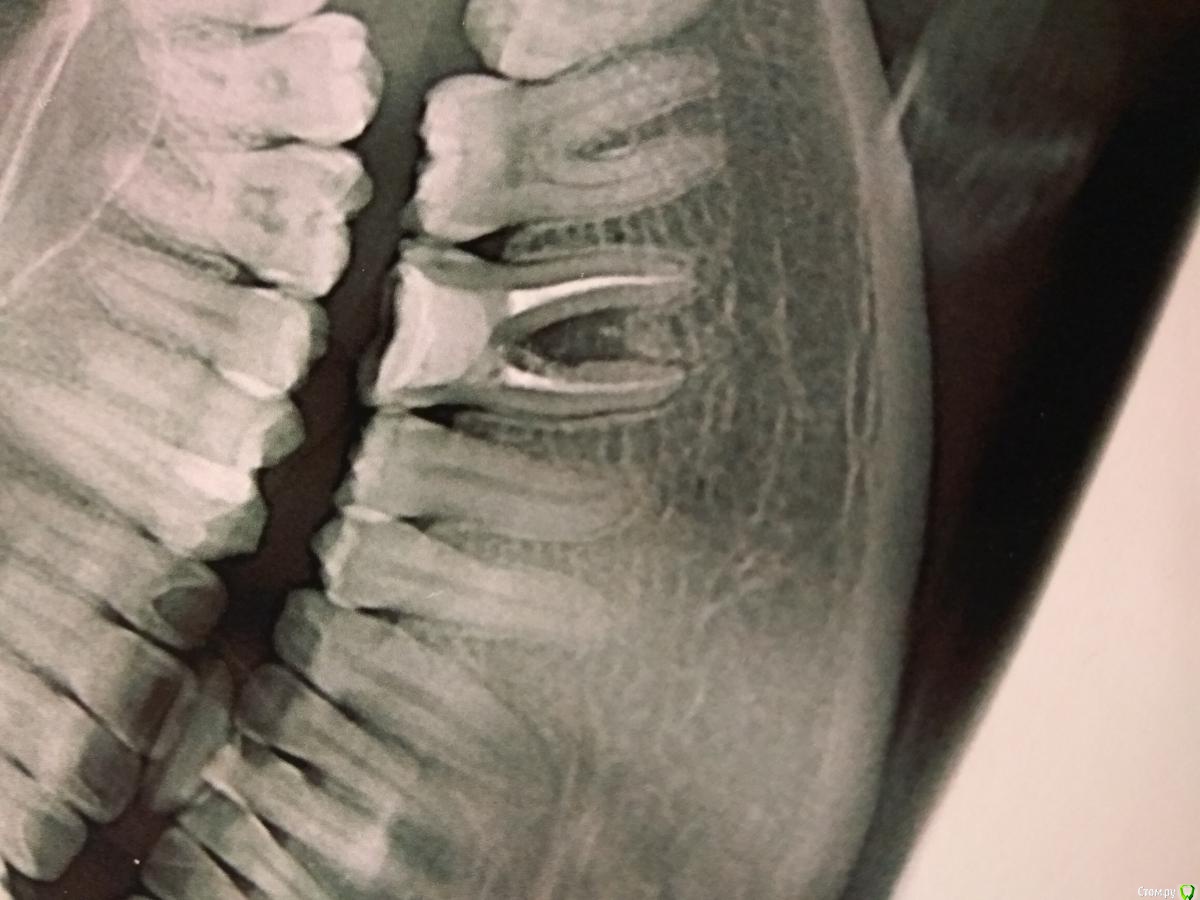

Paganini Опубликовано 20 ноября, 2017 Поделиться Опубликовано 20 ноября, 2017 Приветствую!Раз уж форум создан для общения, получения знаний и советов, то прошу помочь с клиническим случаем.Как я понимаю, в области 36 зуба была перфорация, за которой последовало разрежение костной ткани в области бифуркации, плюс есть расширение периодонтальной щели и прочее... Лечение - удаление.Вопрос: есть ли варианты консервативного лечения, которые дадут положительный результат? Три врача сказали удалять, но я читала, что можно попробовать использовать Pro-poot в области перфорационного отверстия. Или может Каласепт? Или есть еще какие-либо варианты?Реально? Да/нет? Кто пробовал? Или оно того не стоит?:P.S.: что касается этого зуба, то жалоб у пациента нет. Ссылка на комментарий

parallax Опубликовано 24 ноября, 2017 Поделиться Опубликовано 24 ноября, 2017 Народ, а где перфорация? Резорбция да, есть, но свод бифуркации целый. Ссылка на комментарий

makinos Опубликовано 24 ноября, 2017 Поделиться Опубликовано 24 ноября, 2017 Свод целый, а в районе устьев медиального корня насверлено-намазано 1 Ссылка на комментарий

parallax Опубликовано 25 ноября, 2017 Поделиться Опубликовано 25 ноября, 2017 Не было тут перфорации, устья запакованы равномерно. А у резорбции другая причина. Ссылка на комментарий

Л Ю С Я Опубликовано 25 ноября, 2017 Поделиться Опубликовано 25 ноября, 2017 Народ, а где перфорация? Резорбция да, есть, но свод бифуркации целый.Смотрите на устье мед каналов. Вообще без кт в таких случаях больше догадки Ссылка на комментарий

parallax Опубликовано 25 ноября, 2017 Поделиться Опубликовано 25 ноября, 2017 Смотрите на устье мед каналов. Вообще без кт в таких случаях больше догадки Была бы перфора, силер был бы в этой перфоре. А так медиальные каналы запломбированы в идеальном конусе. Да и следов закрытия перфорации не наблюдается (тот кто лечил зуб 5 лет назад не совсем же дебил, чтобы оставить перфорацию незакрытой).А так да, нужно делать КТ. Ссылка на комментарий

parallax Опубликовано 25 ноября, 2017 Поделиться Опубликовано 25 ноября, 2017 Совсем не обязательно , что там должен быть силер.Самое лучшее композит. В худшем случае вонючка))) Но там нет ни композита, ни СИЦа, ни силера, ни перфорации. Только резорбция (ХЗ, может уже и вонючка). Ссылка на комментарий

Л Ю С Я Опубликовано 25 ноября, 2017 Поделиться Опубликовано 25 ноября, 2017 В принципе не важно : резорбция , перфорация. Однозначно, есть нарушение целостности стенки корня и микробы 2 Ссылка на комментарий

vse32 Опубликовано 25 ноября, 2017 Поделиться Опубликовано 25 ноября, 2017 Но там нет ни композита, ни СИЦа, ни силера, Откуда такая уверенность? Есть куча не рентгенконтастных материалов. Те же МТА и аналоги, кальций, композиты (Градия например) не контрастны. Все это в вонючем виде там может находиться. Ставлю на МТА и аналоги или кальций. Ссылка на комментарий

parallax Опубликовано 25 ноября, 2017 Поделиться Опубликовано 25 ноября, 2017 Вообще-то, оксид висмута рентгеноконтрастен. И покажите мне идиота, который будет закрывать перфорейшн Градией? То же касается кальция. Ставлю на то, что там нет перфоры. Там другая проблема, из-за которой и получилась резорбция и из-за которой зуб подлежит удалению. Ссылка на комментарий